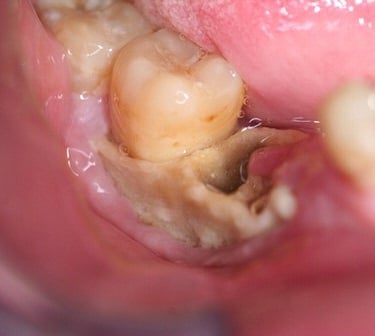

Osteonecrosis de los maxilares

La osteonecrosis de los maxilares es la muerte del hueso mandibular o maxilar debido a una disminución del flujo sanguíneo, a menudo asociada con ciertos medicamentos o radioterapia.

Los pacientes pueden notar dolor, hinchazón y exposición del hueso.

El tratamiento incluye la eliminación del hueso muerto y medidas para mejorar la circulación sanguínea.